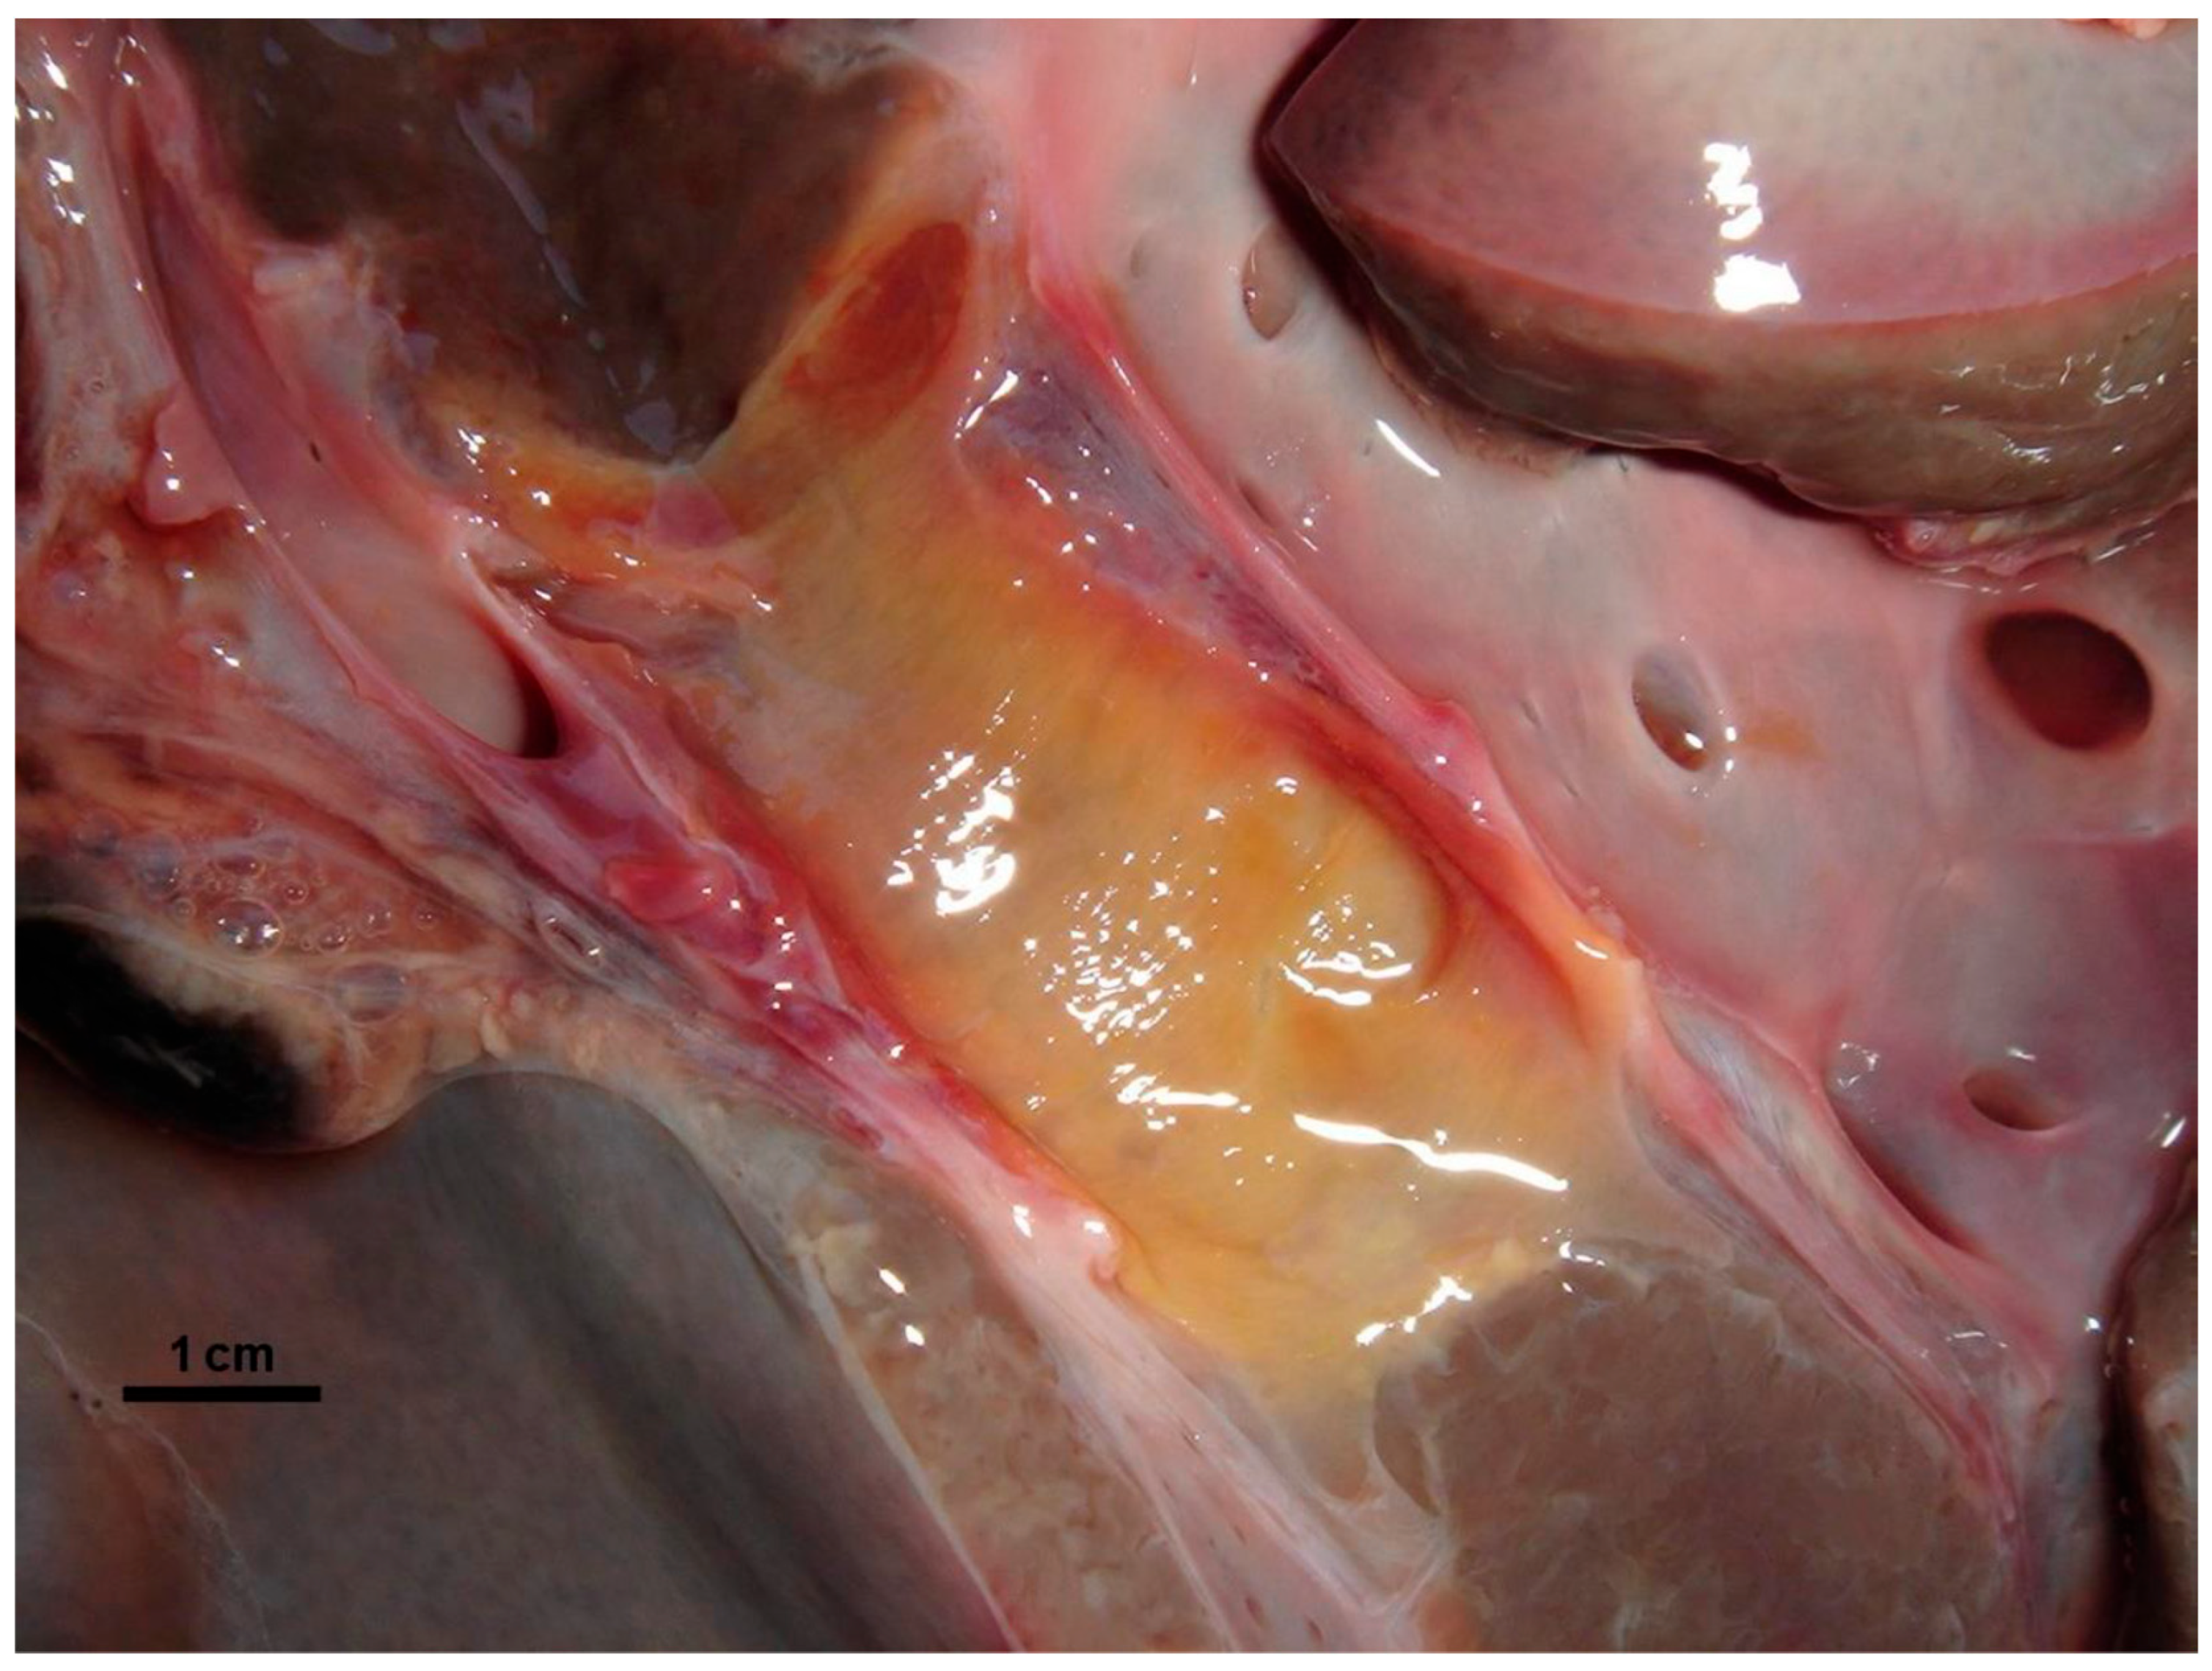

3.1. Necropsy